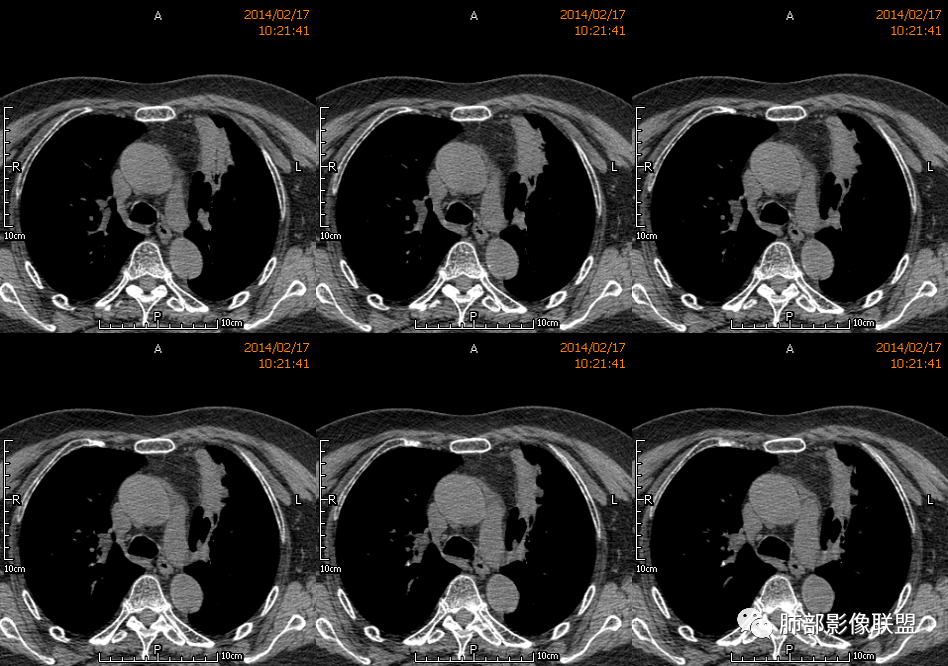

薏米: 老年女性,急性起病,咳嗽,咳痰,咯血,白细胞低,胸部CT提示左肺上叶可见一团块样密度增高影,边缘平直,部分略有膨隆,内可见支气管进入后截断,小的空洞,血管造影,坏死,明显强化,周边可见少许索条,考虑炎性病变,肺脓肿可能。鉴别结核,隐球菌。

一切∮随缘: 定位:肺内,左肺上叶肿块,呈长条状,平行血管束生长,边缘分叶,平扫密度均匀,增强后不均匀强化,可见低密度坏死,近段支气管及血管穿行病灶内,远端堵塞支气管,血管似有破坏,周围散在点状小结节,及纤维索条影,考虑恶性:腺癌,类癌,淋巴瘤。鉴别结核及隐球菌。

红星: 老年女性,咳嗽咳痰10天,痰中带血4天。左肺上叶前段胸膜下肿块影,沿支气管方向走行以膨胀生长为主,局部有收缩改变,支气管血管绝断,中间有小片状的坏死及小的空洞影,增强扫描病灶明显的强化,病灶周围网格状的小叶间隔增厚。拟左肺上叶前段浸润型腺癌并癌性淋巴管炎。鉴别诊断结核肉芽肿。

秦化君: 左肺上叶前段胸膜下软组织密度肿块影,边缘清晰,部分边缘膨隆,纵隔缘弧形内凹,脂肪界面清晰。肿块中心密度减低,支气管进入病灶后截断,似有扩张表现,病灶周围可见小叶间隔增厚,斑片影,近端支气管似管壁增厚。增强后明显强化,中心见低密度区。考虑:1.肉芽肿性炎?2.IMT?3.淋巴瘤?

傅昌瑜: 老年女性,咳嗽咳痰10天,痰中带血4天。左肺上叶前段胸膜下肿块影,沿支气管方向走行,膨胀生长为主,局部边缘似有收缩改变,中间有小片状的坏死,支气管进入,增强扫描病灶明显的强化,血管走形较自然(血管漂浮征?),病灶周围网格状的小叶间隔增厚。考虑淋巴瘤可能性大,注意鉴别炎性肉芽肿及肺腺癌。

水晶石头: 患者老年女性,咳嗽咳痰10天,痰中带血4天余。查血常规白细胞低;肿瘤标志物、凝血功能正常;血生化:蛋白低;C反应蛋白、血沉稍升高。胸部CT:左肺上叶前段胸膜下沿气管支气管走形肿块影,长轴与胸膜平行,见分叶、毛刺、支气管截断、空泡征象。增强明显强化,且见血管造影征及病灶内小灶低密度坏死区。左肺上叶尖后段见一结节灶。综合考虑恶性病变可能大,腺癌或淋巴瘤可能。鉴别诊断肺脓肿。

尘缘: 老年女性,咳嗽咳痰10天,痰中带血4天,白细胞及中性粒明显减低,轻度贫血。影像表现:左上叶肿块,边缘膨隆,局部平直,支气管稍扩张,进入后远端堵塞,内见小空洞及不规则坏死区,增强后强化明显,坏死边界较清,并见环状强化区,内部血管走行自然,周围见小叶间隔增厚呈大网格征。初步诊断:慢性炎性伴脓肿形成及肉芽组织增生。鉴别淋巴瘤及腺癌,先抗炎治疗后复查或直接穿刺明确。

张延军: 左肺上叶前段软组织影,偏下缘见充气支气管,部分支气管壁与肿块近端增厚狭窄。实性部分见血管穿行,边缘平直并局限性凹陷,增强扫描内见斑片状低密度区,界不清,实性部分中度强化,病变外宽内窄,基底贴于胸壁,周围肺组织内见条片状密度增高影,考虑炎性,结核?腺癌待排。

毛勤香: 老年女性,左肺上叶胸膜下肿块,部分膨隆部分收缩,边缘毛糙模糊,周围少许索片状影,小叶间隔增粗,支气管进入后截断,增强扫描明显不均匀强化,内低密度区无明显强化,血管走行尚可,首先考虑感染性变并脓肿形成,鉴别淋巴瘤,建议抗炎后复查。

宇宙星空: 外大内小,近端支气管壁增厚,爬树征,内部坏死不均匀,都比较典型了。支持结核,鉴别炎性肉芽肿、慢性脓肿。

王崇军: 老年女性,咳嗽咳痰10天,痰中带血4天。左肺上叶前段胸膜下 肿块影及段形态密度增高影,沿支气管方向走行,膨胀生长为主,局部有收缩改变,支气管进入并闭塞,中间有小片状的坏死及小的空洞影,空洞漂浮在坏死边缘,增强扫描病灶明显的强化,坏死边界清楚,似乎有轻度强化环,病灶周围网格状的小叶间隔增厚及小结节影,外侧胸膜呈糊墙改变。考虑为肺脓肿,这么大的病灶,竟然没有发烧,白细胞低,CPR轻度升高,均与脓肿不符,所以恶性待排,短期抗炎治疗后复查,病灶没有变化,脓肿就可以排除,恶性基本可以确定。

空格: 临床特点:老年女,血糖略高,低蛋白血症,白细胞低,提示有免疫下降的存在。机会性感染存在机会。黄浓痰一般常见于炎性病变,痰中带血则肿瘤多见,两厢pk,觉得黄脓痰胜,除非肿瘤继发感染一般不会黄脓痰。影像:一 、良性征像:1.病灶整体是个尖端指向肺门的三角形病灶;2.胸膜平直,胸膜外少量液体糊墙;3.支气管未见明显截断,内壁毛糙?4.近端支气管弥漫性增厚,结核脓痰咯出,看做引流支气管;5.多个层面病灶呈直边征,多角征,无明显分叶;6.病灶内坏死边缘光整,伴小气泡。小叶间隔增厚光滑锐利,无结节,不太像癌淋。二、恶性征像:部分层面向胸膜外突,略有占位效应。总体考虑感染性病灶,霉菌可能。结核抗体阴性,可以排除?

刘和林: 老年女性,咳嗽咳痰10天,痰中带血4天。左肺上叶前段胸膜下 肿块影,沿支气管方向走行,膨胀生长为主,局部边缘似有收缩改变,中间有小片状的坏死,坏死区内见小气泡,支气管进入、部分填充、部分末端稍显扩张,增强扫描病灶明显的强化,周围肺不干净,其上肺见小叶间隔增厚。肺癌、淋巴瘤、炎性肉芽肿?肺癌:支气管末端稍扩张,周围类似树芽征改变,不太符合。淋巴瘤:数个小气泡,明显强化,周围树芽征样改变,不太符合。

王武章: 灶内低密度,花环样强化,血管穿行漂浮,邻近胸膜并未广泛增厚也未牵拉但接触面脂肪密度略高且模糊。考虑IMT,鉴别慢性炎症相关的非特异性瘤样病变。